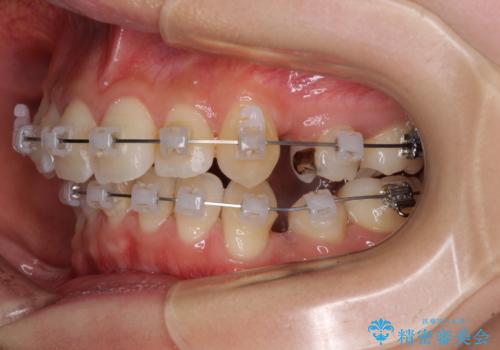

- 矯正装置

- クリアブラケット

- 1年5ヶ月

- 前歯の叢生と八重歯を気にして来院された患者様です。

叢生が強く、奥歯の咬合も左右差が大きかったため、上下左右4本を抜歯して、ワイヤー矯正を行うこととしました。

20歳前後と年齢が若かったため、非常にスムーズに歯列が整い、1年半をかけずに治療を終えることができました。